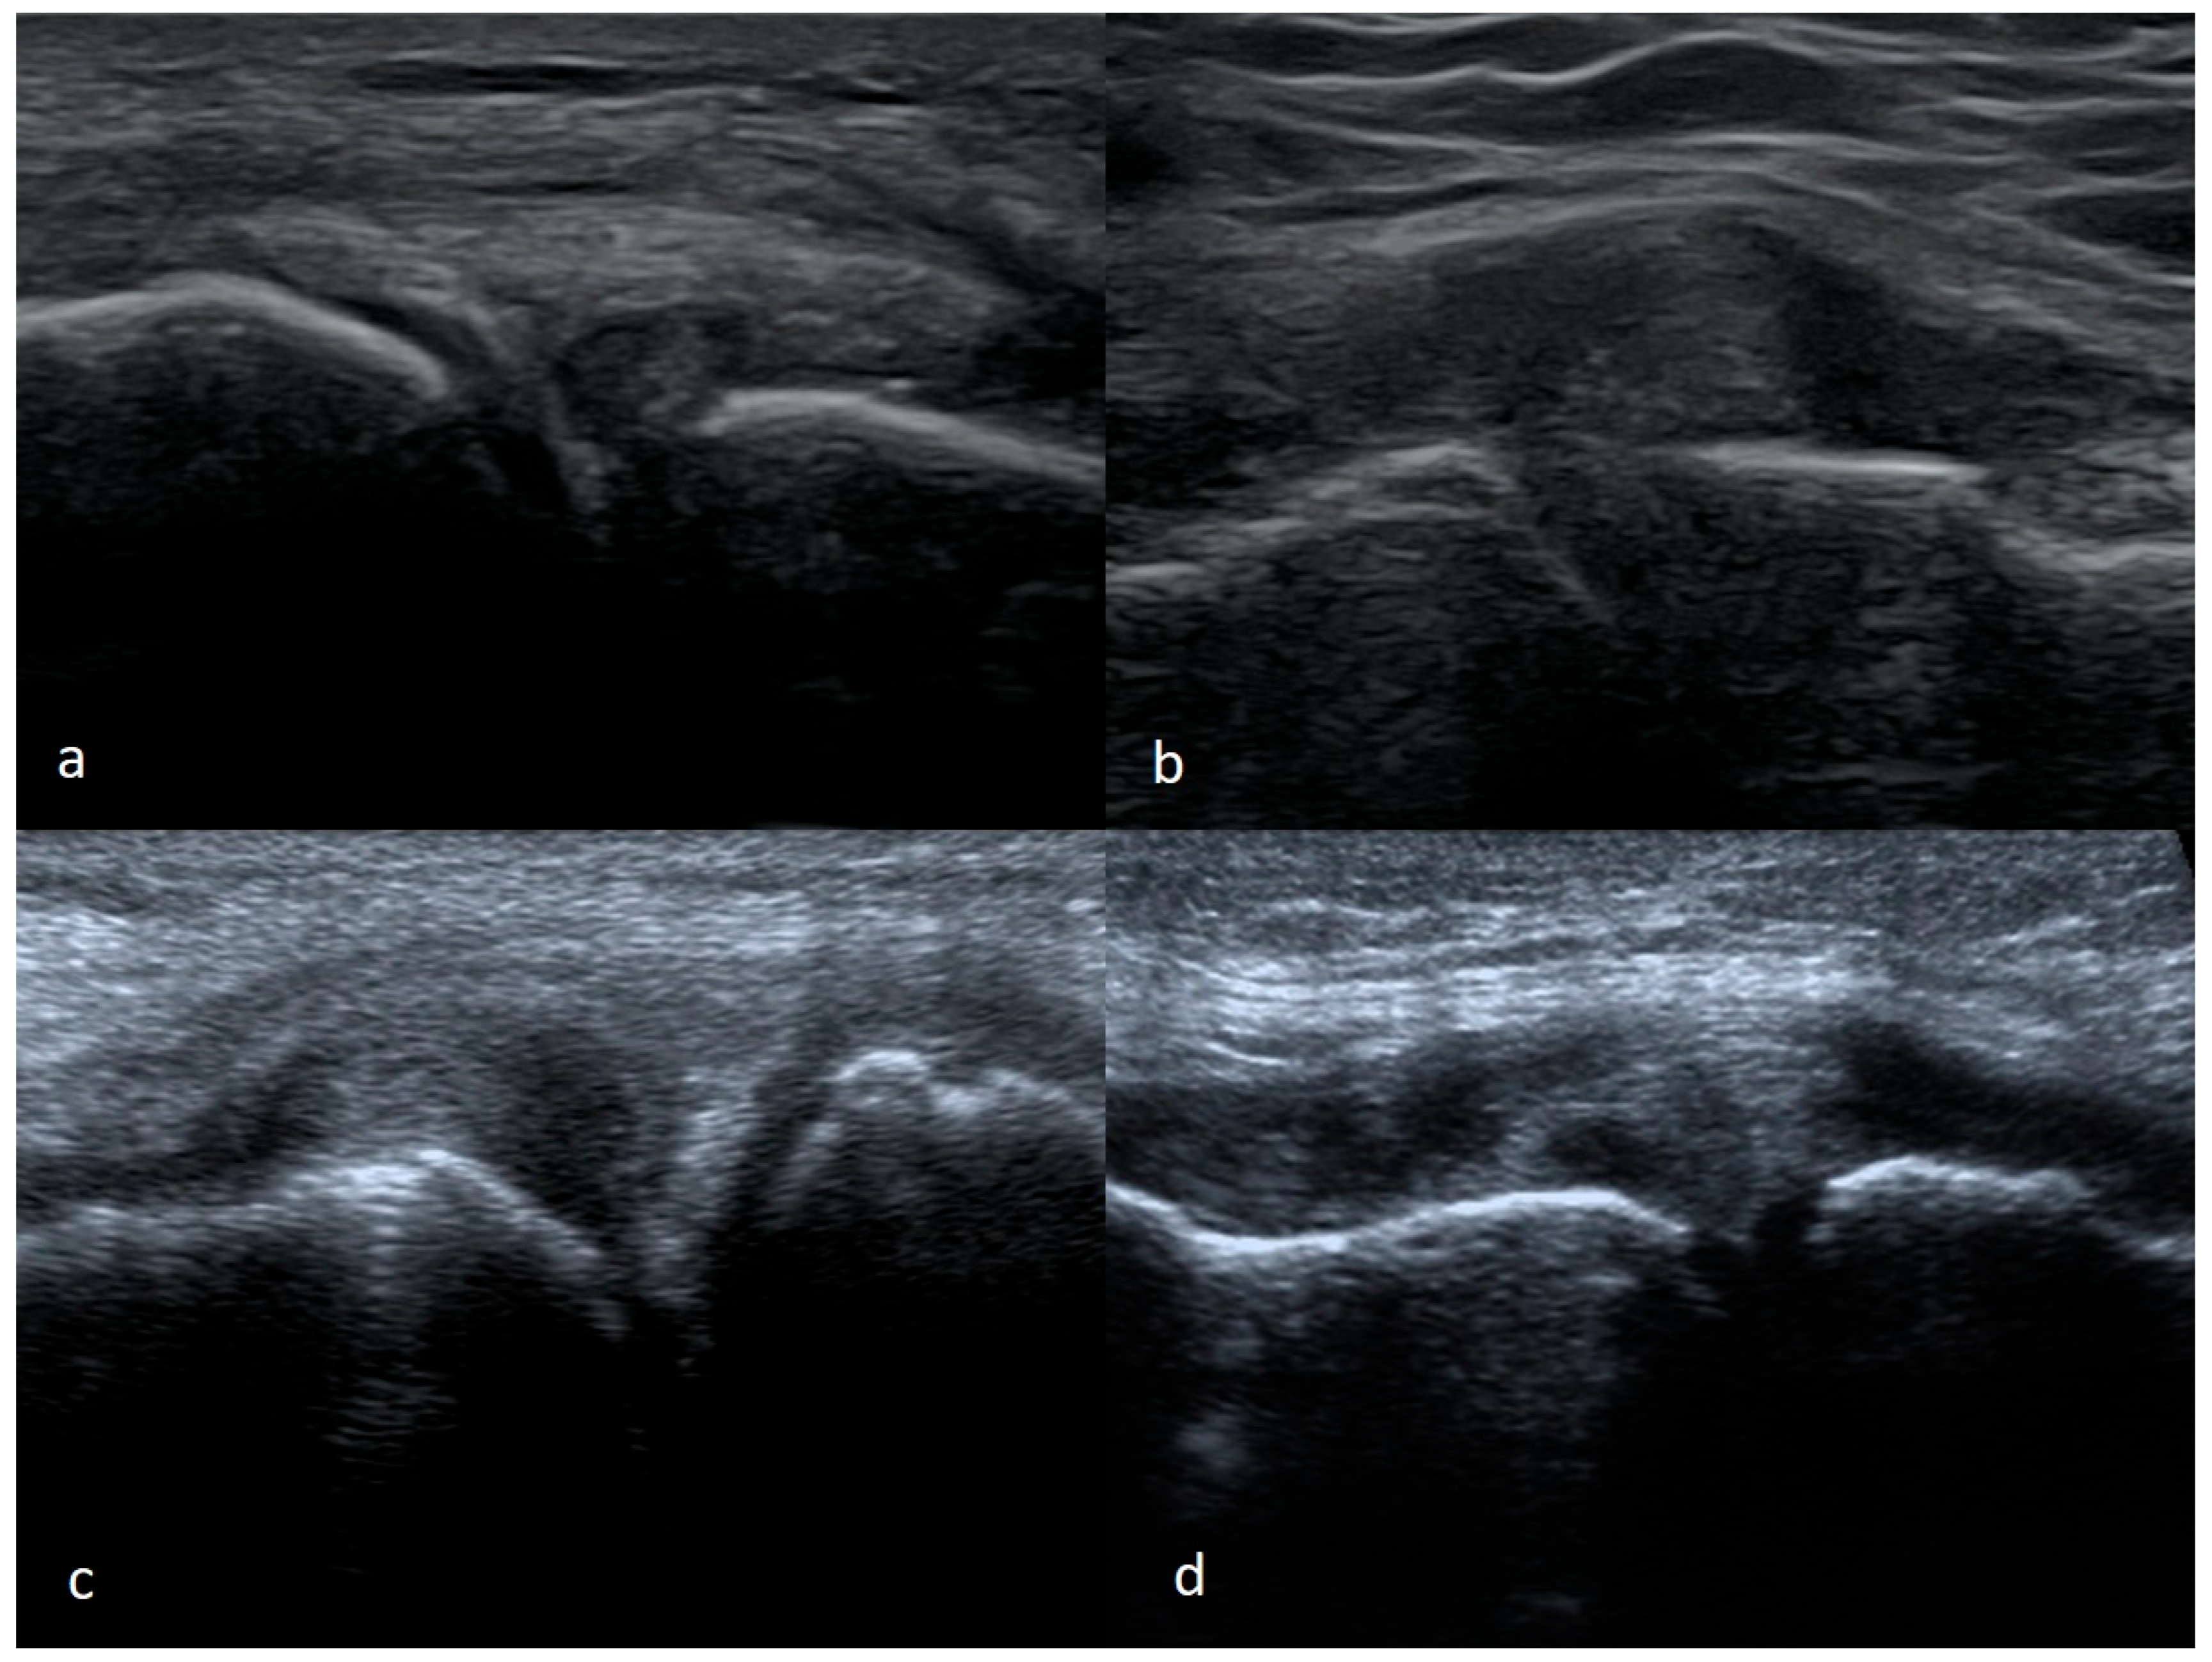

3.1.4. Meniscal Flap Tears

3.1.5. Degenerative Changes of Menisci